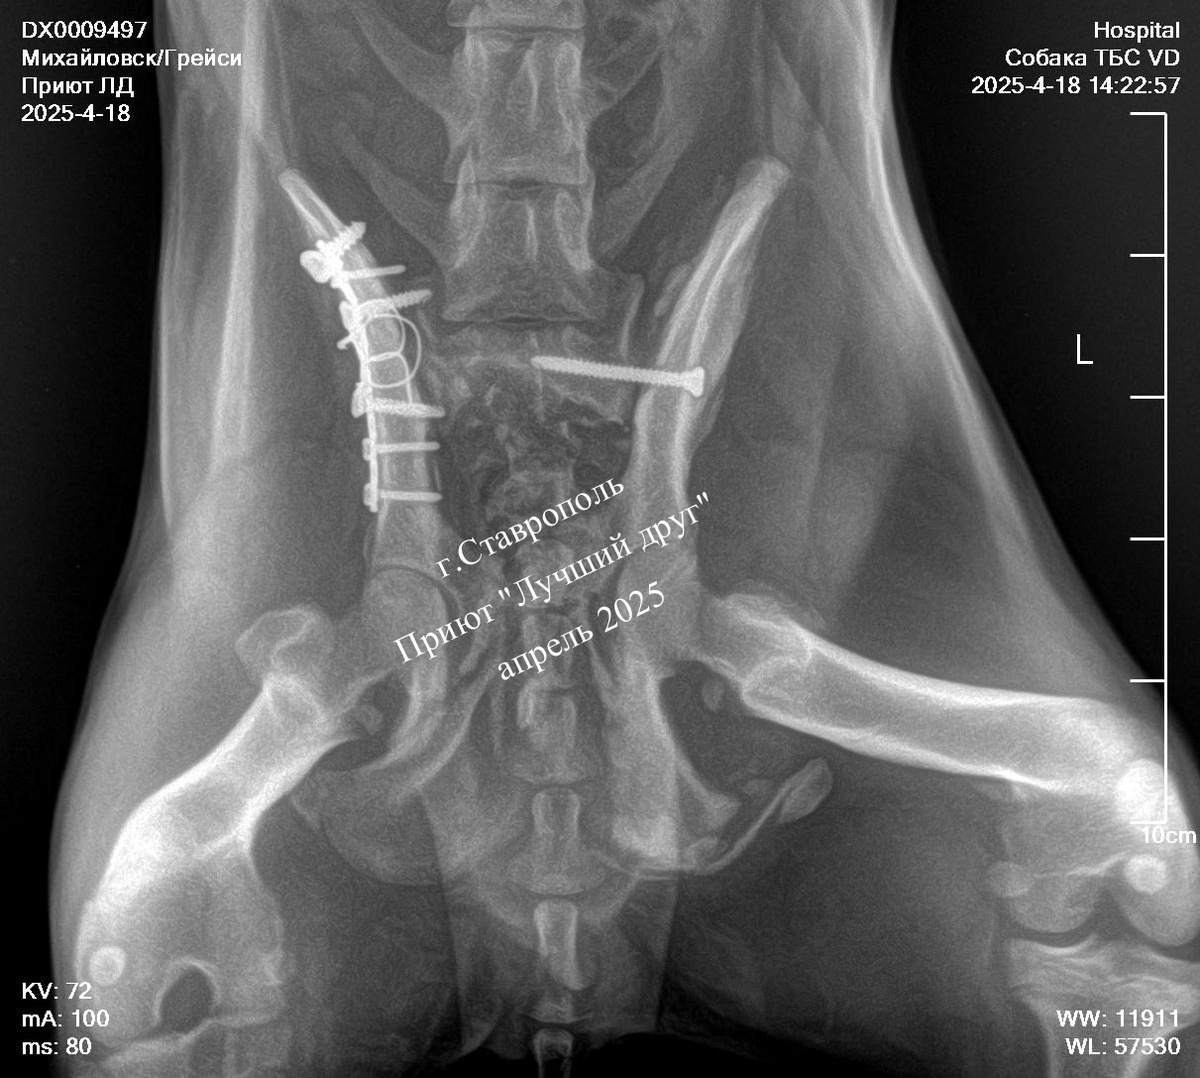

Жертва лихача. Грейси выжила и потихоньку восстанавливается!

У собаки был сломан таз в нескольких местах, но внутренние органы не пострадали. Оперировали Грейси в два этапа. Сначала провели стабилизацию левого подвздошно-крестцового вывиха, через двое суток остеосинтез правой подвздошной кости, и через несколько дней собаку выписали в приют долечиваться. После аварии прошло уже много времени, Грейси поправилась и на очередном приеме в клинике хирург сказал, что у малышки все хорошо.

Винты в тазу остаются у Грейси пожизненно, тазовые кости после операции стоят ровно, кишечник не передавливают, проходимость хорошая. Нужно побольше движения красотки и она переехала из комнаты в вольер к друзьям, там ей и веселее, и активности более чем достаточно.